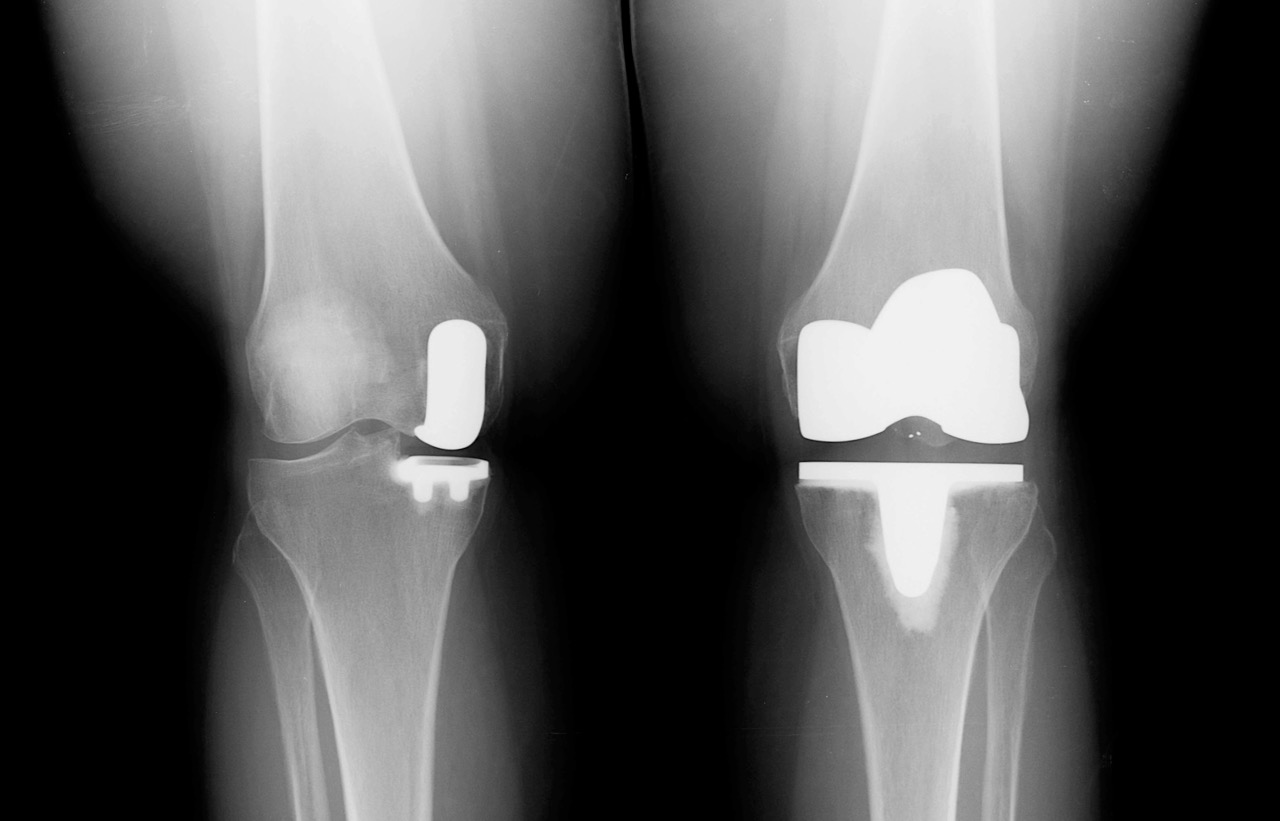

Фотографии и примеры протезирования коленного сустава